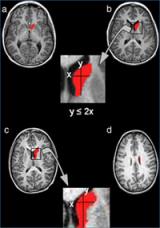

En rojo está pintado el nucleo caudado, en la parte superior la cabeza y en la parte inferior el cuerpo. La fórmula indica el método para separar la cabeza del cuerpo.

El primer estudio citado por el "Consensus report" fue publicado en 2008 en la revista Psychiatry Research: Neuroimaging. El grupo fijó su investigación en el núcleo caudado, una de las principales estructuras cerebrales involucradas en el aprendizaje y la memoria, que tiene tres partes: la cabeza, el cuerpo y la cola. Se había comprobado que el núcleo caudado estaba alterado en los pacientes con TDAH, aunque la literatura previa presentaba resultados contradictorios sobre cuáles eran las alteraciones concretas. El grupo del Dr. Vilarroya descubrió que los pacientes con TDAH presentaban una alteración entre la cabeza y el cuerpo del núcleo caudado que no se veía en los sujetos controles. Con el desarrollo de un nuevo método de segmentación del núcleo caudado, entre la cabeza y el cuerpo se pudo mostrar que los pacientes con TDAH presentaban un núcleo caudado derecho más pequeño, fundamentalmente debido a una disminución en el cuerpo, que no la cabeza, del núcleo caudado.

El segundo artículo citado por la APA, publicado en el año 2010 en la revista Psychiatry Research: Neuroimaging, partió de estos resultados para evaluar la posibilidad de clasificar los pacientes TDAH en base a las diferencias entre la cabeza y el cuerpo de su núcleo caudado. El análisis mostró que el hallazgo presentaba una especificidad del 95% y una sensibilidad del 60%, lo que indicaba que podría ser extremadamente útil para confirmar el diagnóstico de TDAH. Esto abría el camino para usar este descubrimiento como biomarcador de neuroimagen y facilitar un diagnóstico robusto y precoz de este trastorno.

Los estudios posteriores han ido dirigidos a automatizar el método de segmentación del núcleo caudado entre cabeza y cuerpo para permitir un uso clínico rápido y eficiente. En este sentido, se han publicado dos trabajos, uno en la revista Biomedical Engineering Online (2011), donde los investigadores desarrollaron un método automatizado de segmentación del núcleo caudado, basado en análisis de imagen médica y técnicas de aprendiza je automático, y el otro en la revista Computerized Medical Imaging and Graphics (2012), donde los investigadores han optimizado este método para poder separar la cabeza del cuerpo del núcleo caudado, obteniendo resultados muy similares a los de la segmentación manual. Estos nuevos métodos permiten caracterizar de manera precisa y más rápida las principales estructuras cerebrales, a la vez que analizar y hacer un diagnóstico precoz del TDAH.